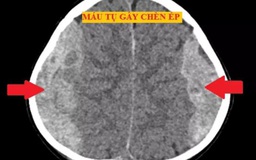

Bé trai 4 tuổi té giường tầng bị chấn thương sọ não nặng